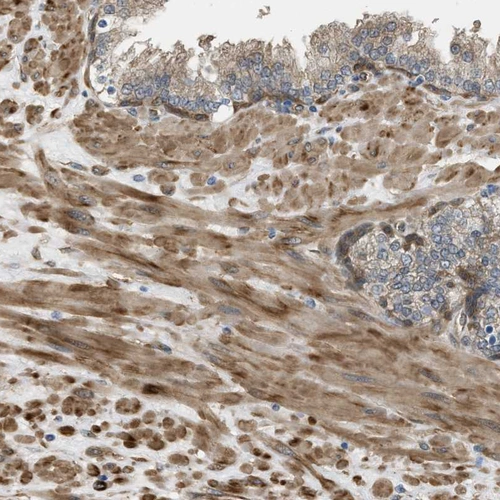

Immunohistochemical staining of human cerebellum, prostate, skeletal muscle and skin using Anti-BAG3 antibody HPA020586 (A) shows similar protein distribution across tissues to independent antibody HPA018493 (B).